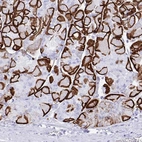

Immunohistochemistry analysis in human cerebral cortex and liver tissues using HPA014784 antibody. Corresponding AQP4 RNA-seq data are presented for the same tissues.

The Anti-AQP4 antibody (HPA014784) specifically targets Aquaporin 4 (AQP4), a vital water channel protein primarily expressed in the brain and spinal cord. AQP4 plays a crucial role in maintaining water homeostasis and is significant in various physiological and pathological processes.